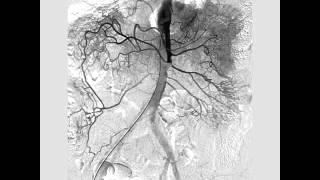

CanadaQBank Superior Mesenteric Artery (SMA) Angiogram

Dr. Rob Williams (Interventional Radiologist) demonstrating how to perform a SMA (Superior Mesenteric Artery) angiogram on a Simbionix simulator.